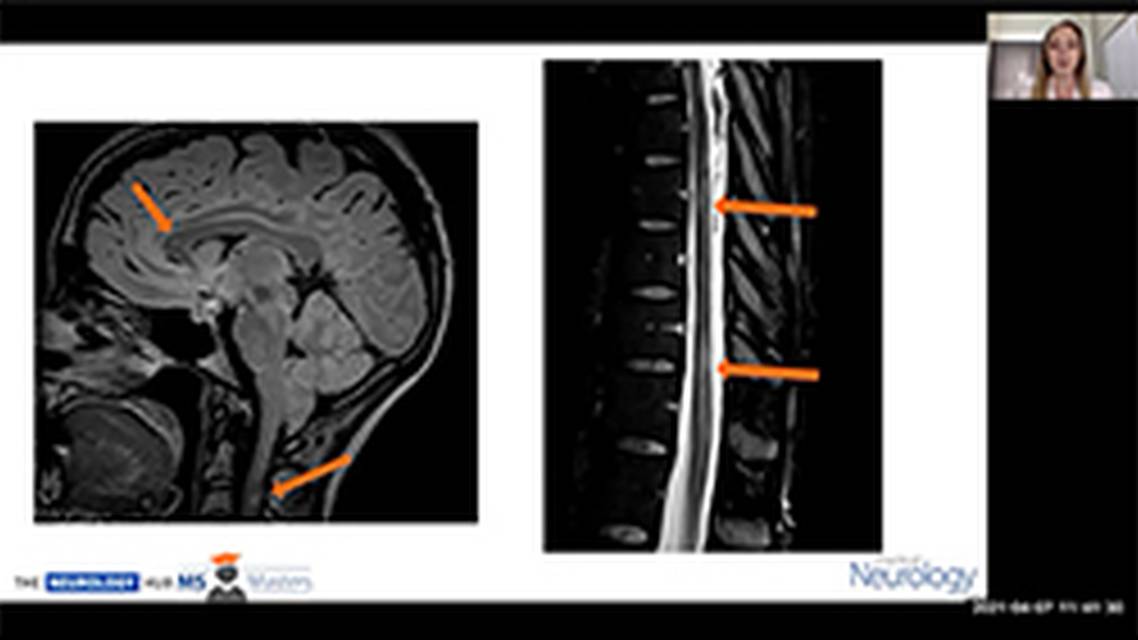

Pregnancy and Multiple Sclerosis